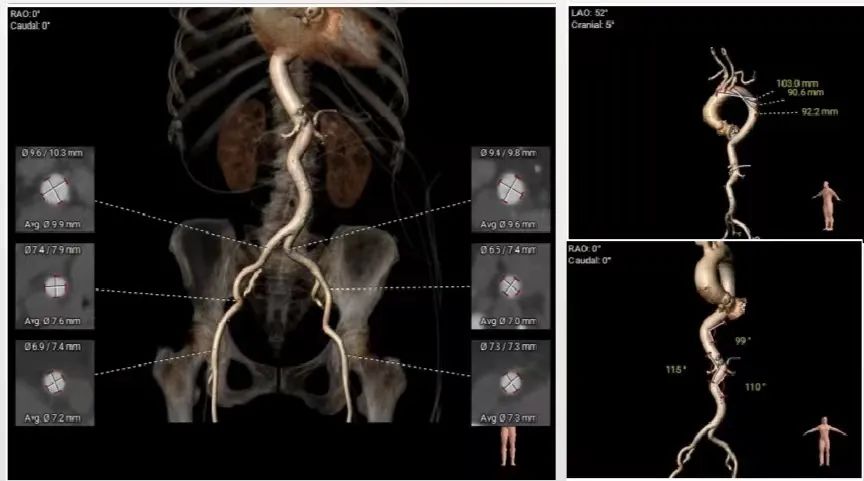

5. 主动脉瓣环与水平夹角62°,横位心,主动脉弓距及弓部夹角尚可;

6. 双侧股髂动脉无明显钙化迂曲、官腔内径可,整体入路直径良好。

外周血管及主动脉弓解剖: